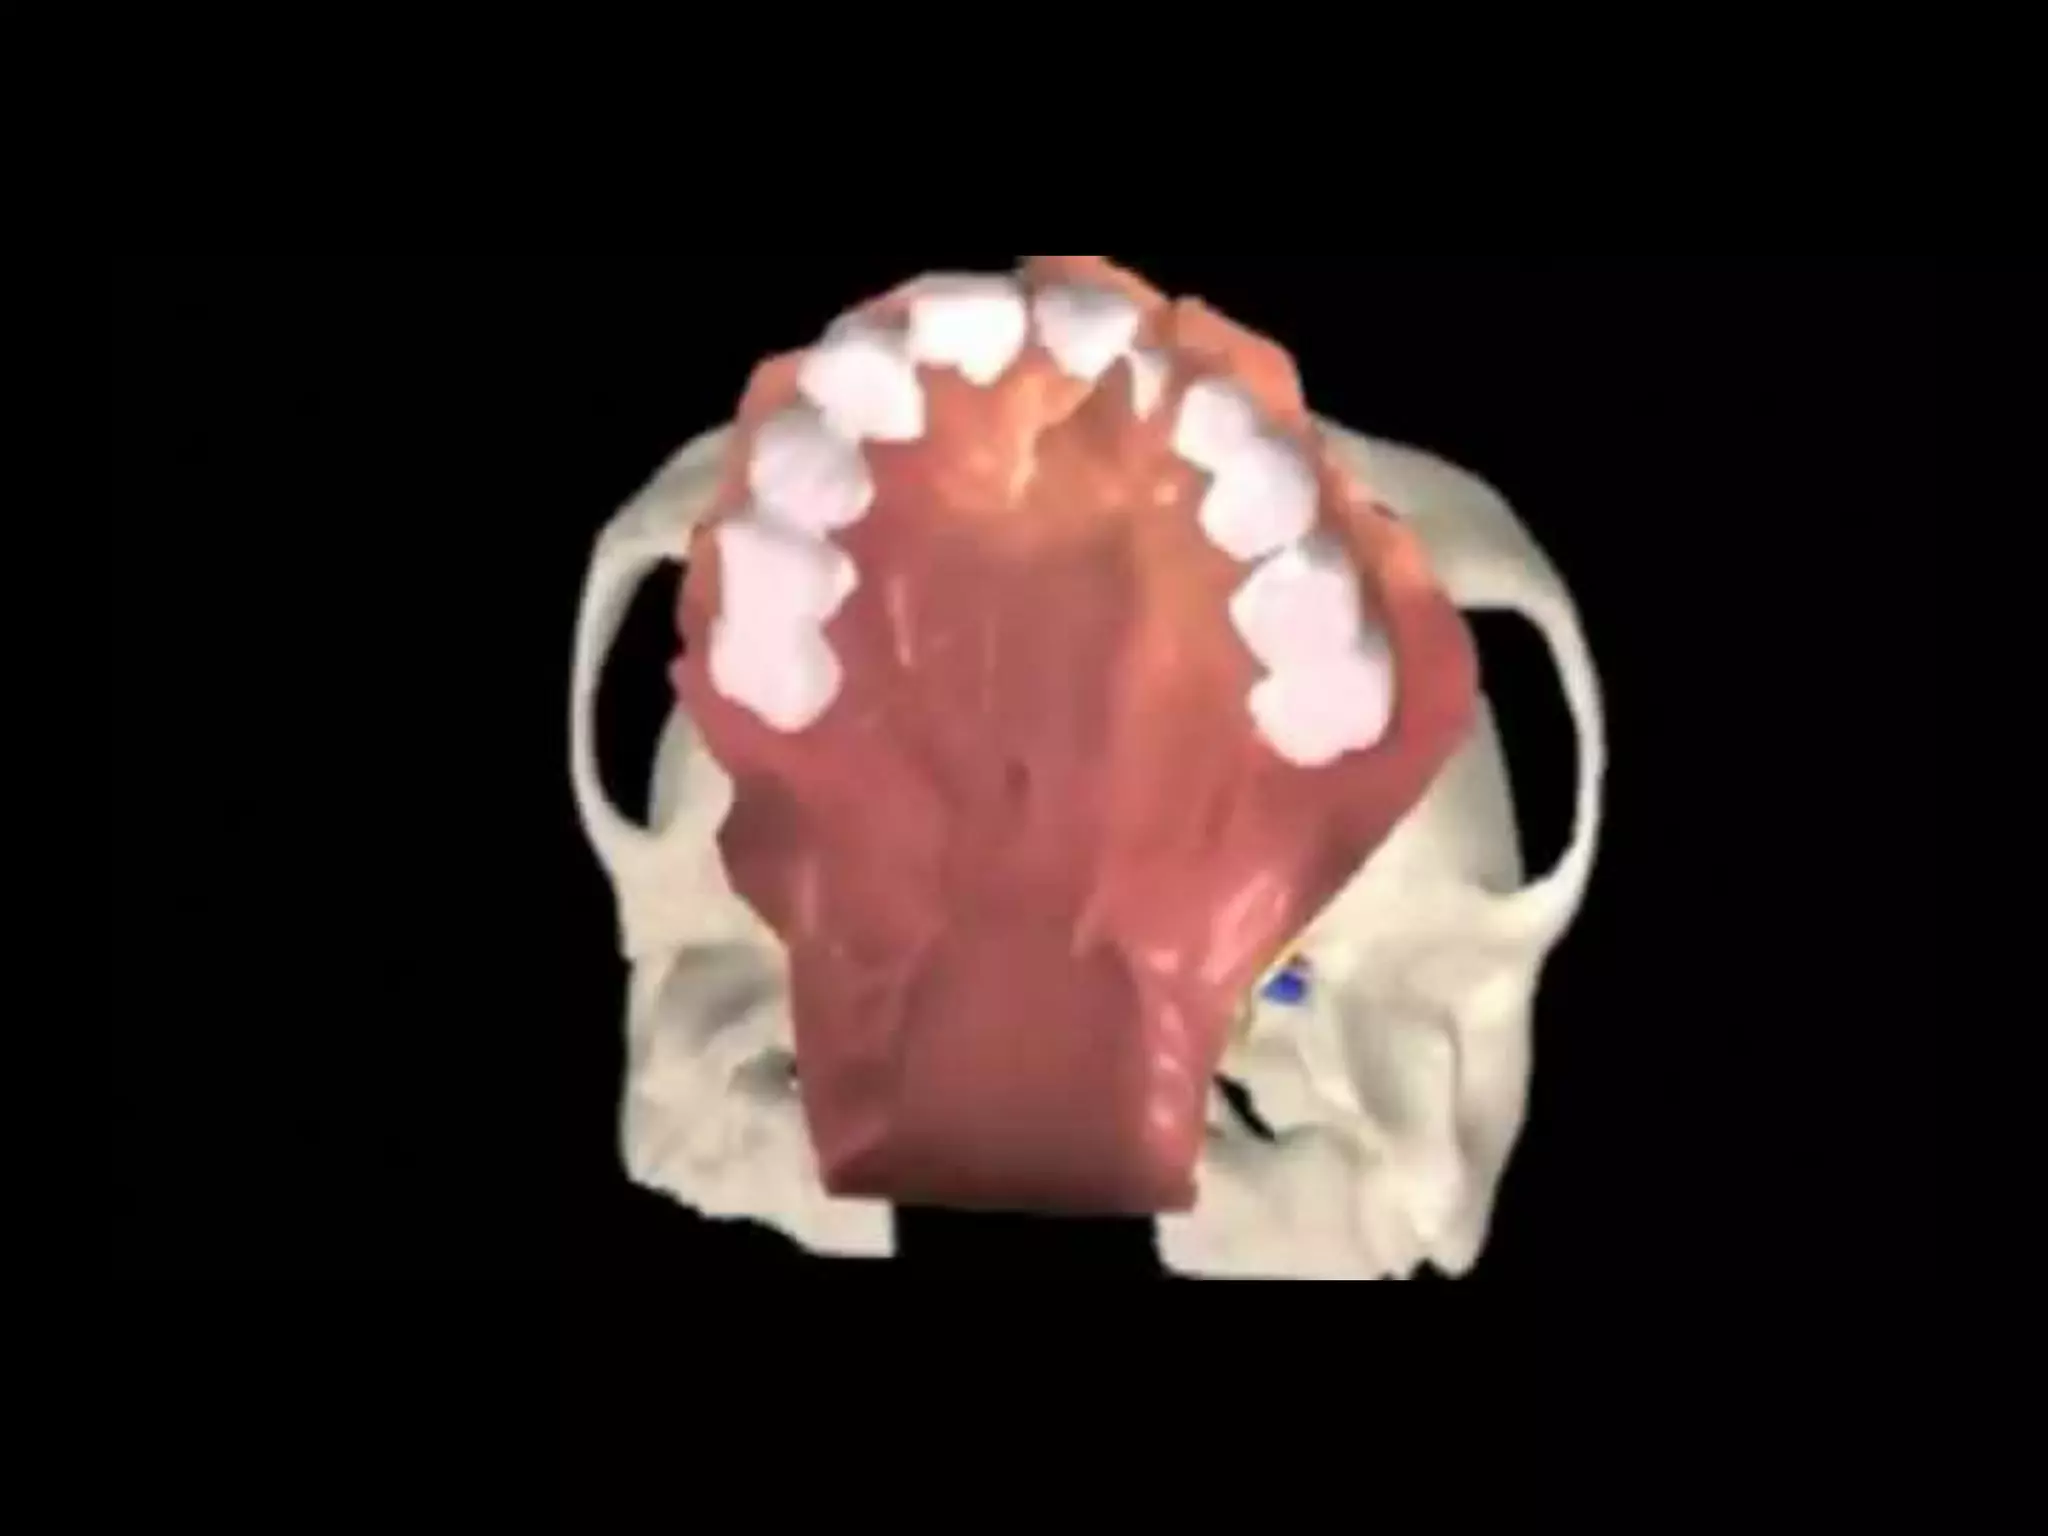

Classification

Classification  Nagpur classification ◦Group I – cleft lip only ◦ Group Ia – cleft lip + cleft alveolus ◦ Group II – cleft palate only ◦ Group III – cleft lip + cleft alveolus + cleft palate